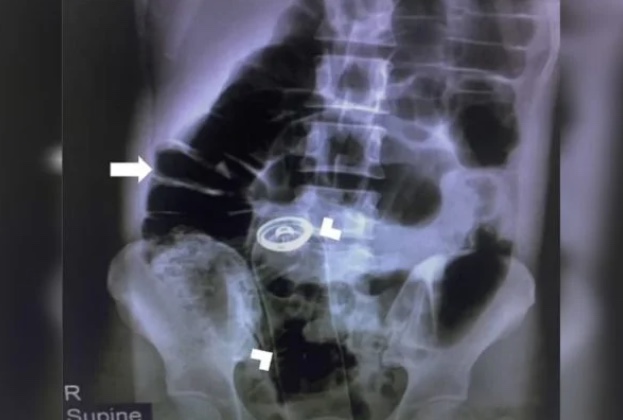

O desodorante foi encontrado por meio de um raio-x, e imediatamente, foi realizado um corte no estômago do iraniano, que estava com dores intensas.

Após a retirada da embalagem de 18 centímetros, o homem ficou no hospital mais dois dias, e foi liberado.